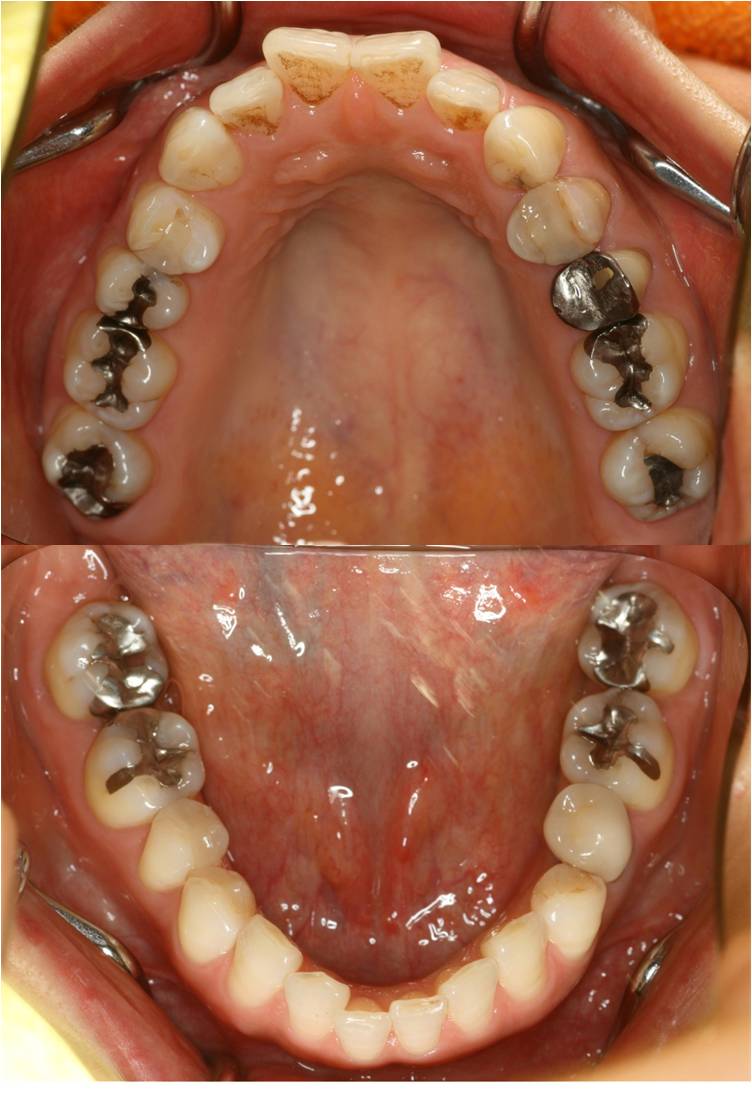

術前

http://www2.ha-channel-88.com/bbs/upimg/?l=2964

術後

http://www2.ha-channel-88.com/bbs/upimg/?l=2963